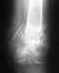

так выглядит моя рентгенограмма, что можете сказать и посоветовать? Заранее благодарен.